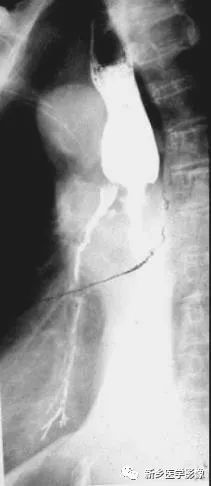

中段食管癌并發食管氣管瘺鋇餐造影圖像

吞鋇后食管中段狹窄,并見支氣管顯影